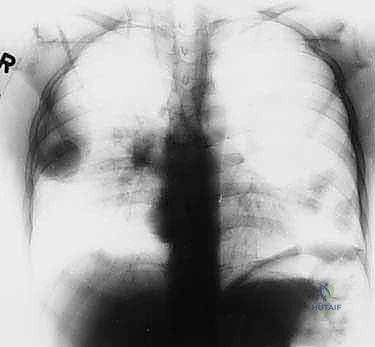

تختلف الأورام في سلوكها البيولوجي بشكل جذري. الأورام الحميدة، رغم أنها قد تسبب ألماً أو تضغط على الأعصاب المجاورة، إلا أنها لا تنتشر إلى أعضاء أخرى. أما الأورام الخبيثة (مثل الساركوما العظمية Osteosarcoma، ساركوما إيوينغ Ewing's Sarcoma، أو الساركوما الغضروفية Chondrosarcoma)، فلها قدرة تدميرية موضعية عالية وقابلية للانتشار (الانبثاث) إلى الرئتين أو عظام أخرى.

- الأشعة السينية (X-ray): الخطوة الأولى لتقييم العظام وتحديد نمط التدمير العظمي.

- الأشعة المقطعية (CT Scan): ضرورية لتقييم القشرة العظمية والتكلسات داخل الورم، وللبحث عن أي انتشار في الرئتين.